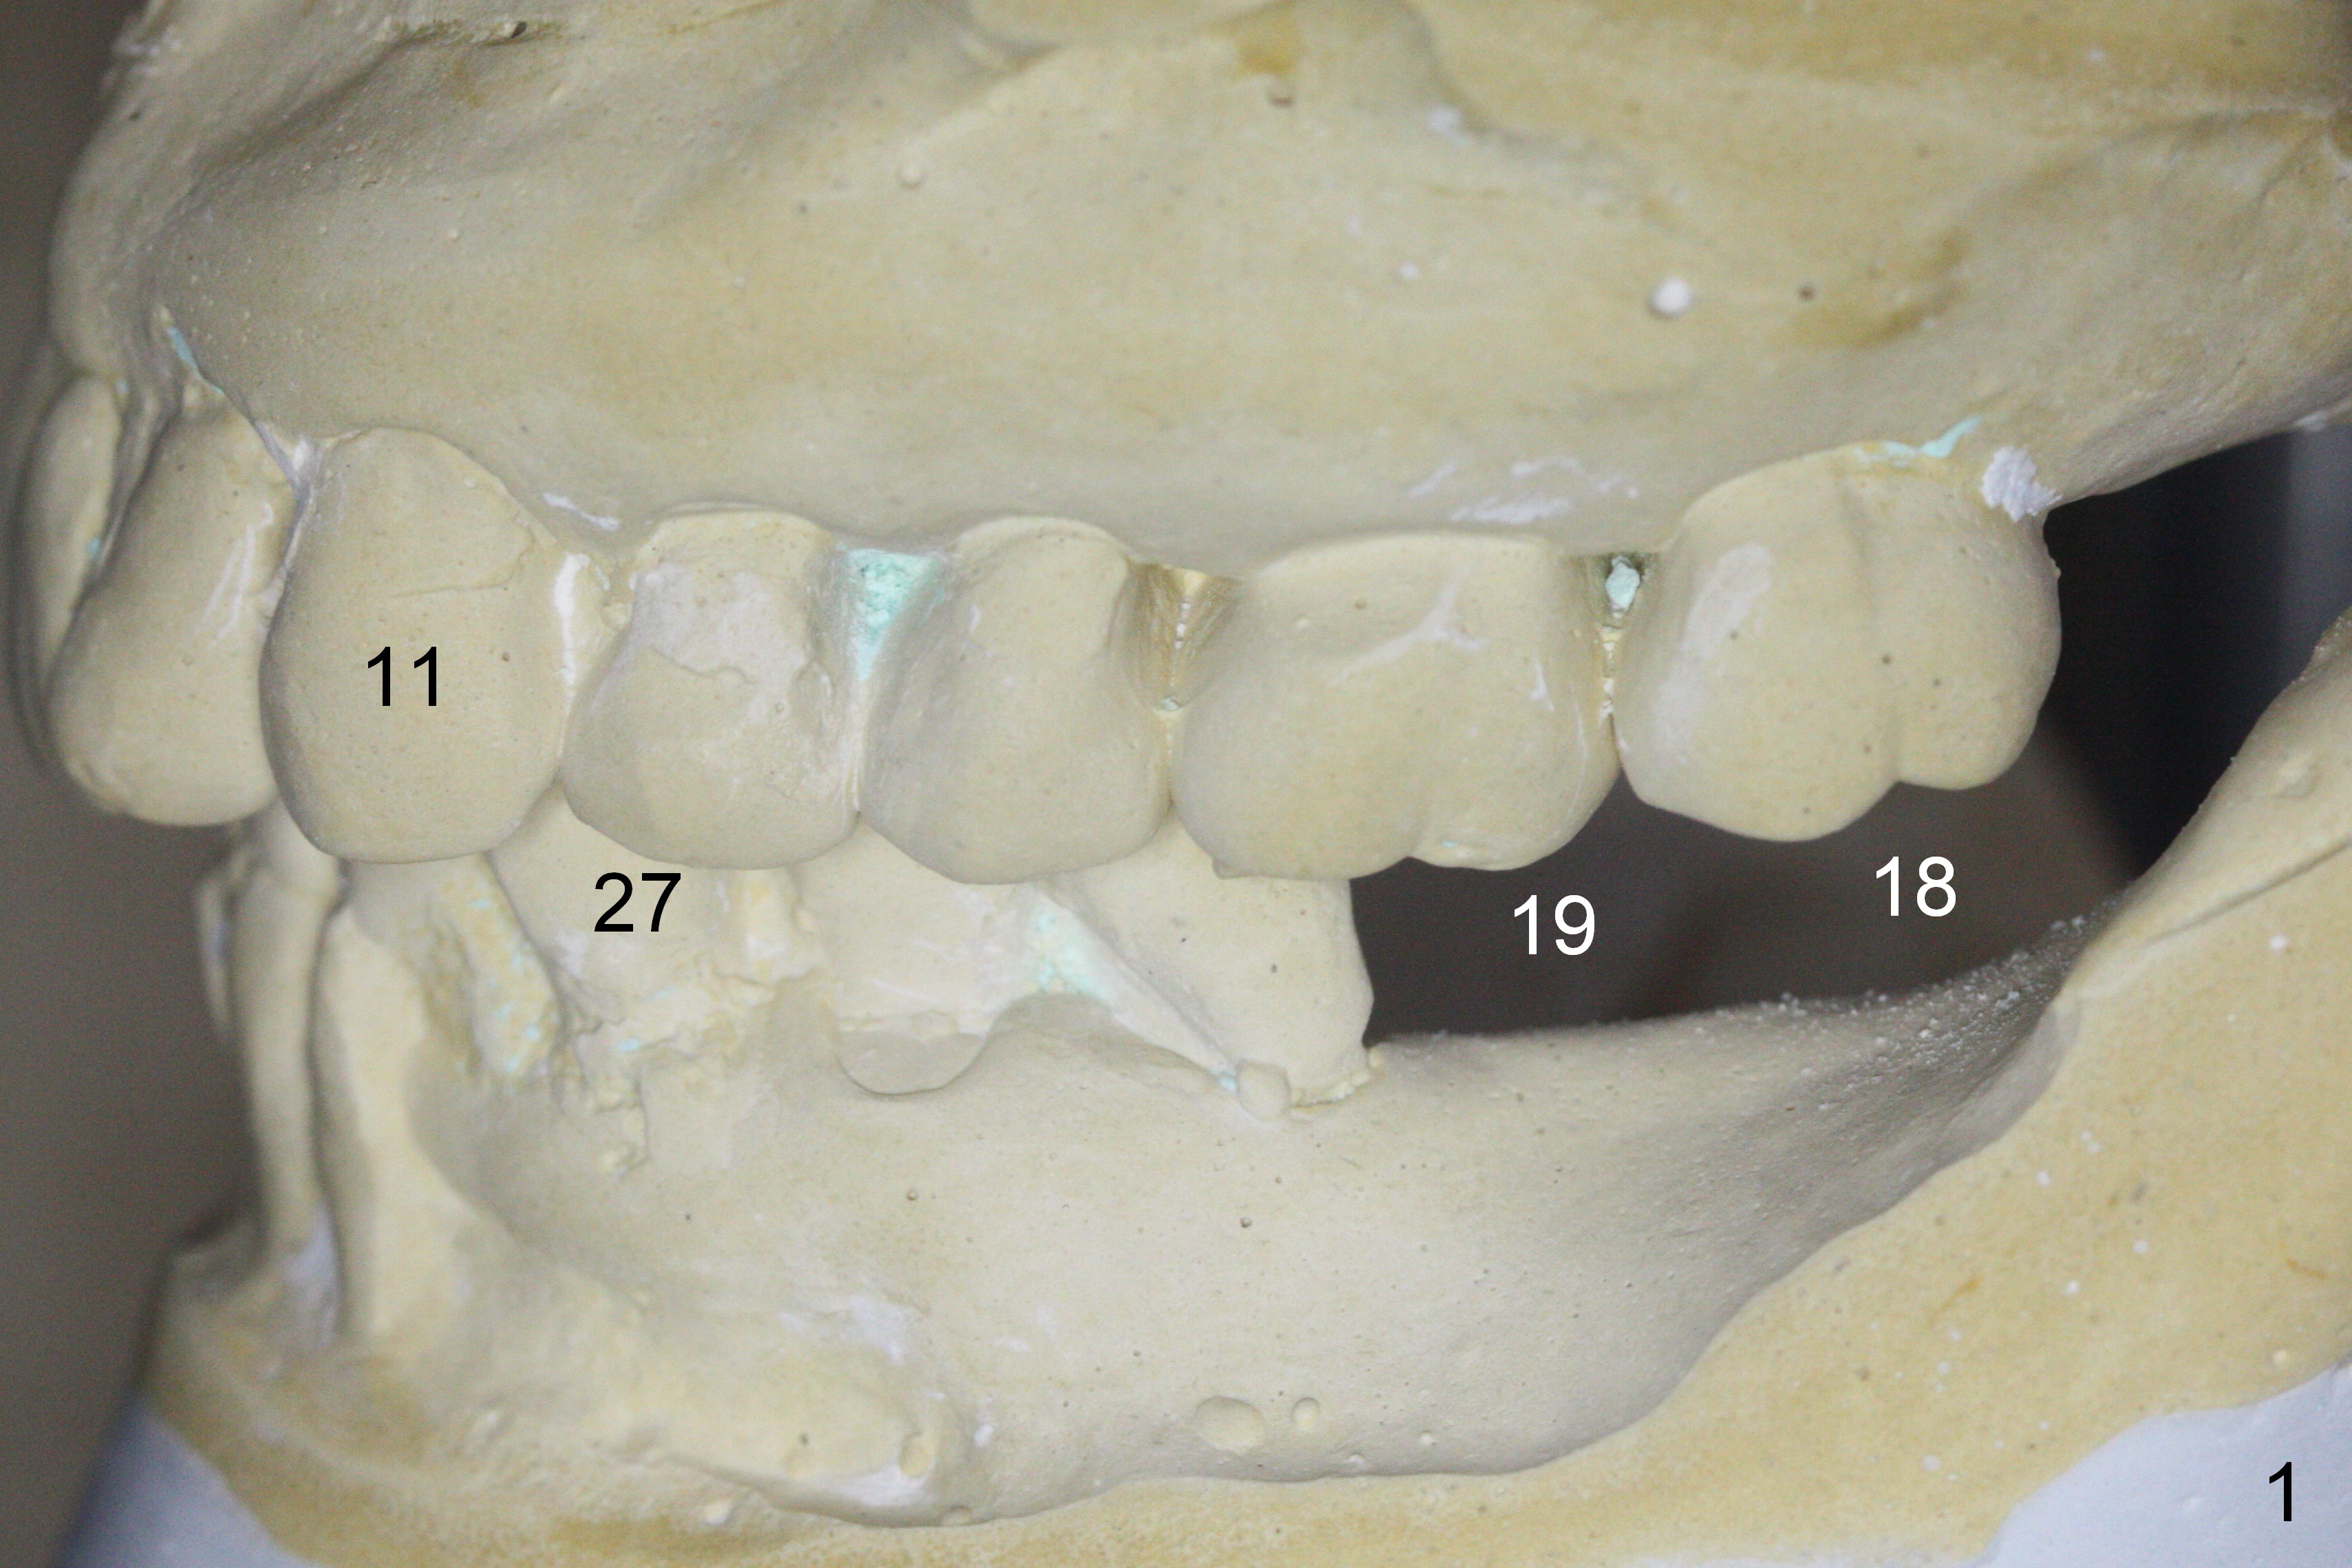

A 73-year-old woman requests implant restoration at #18 and 19 (Fig.1). The left posterior occlusion is Class II (Fig.1,2). The right one is Class I because of small dimension of the restoration at #30 (Fig.3 (premolar)). The normal size of the lower left molars will keep Class II occlusion (Fig.4), which may create cheek bite posteriorly. To correct the occlusion to Class I, move osteotomies to the mesial aspect of waxed-up molars (Fig.6 white circles). Finally a premolar crown and the 1st molar will be placed at #19 and 18, respectively. The supraerupted opposing molars (Fig.5 arrowheads) will to be adjusted when the abutments are placed at the lower molars.

The lady has taken Fosamax for osteoporosis several years. The medicine may cause osteonecrosis. CBCT study does not show sign of osteonecrosis apparently (Fig.7-9). Since the ridge at #19 is narrow (Fig.8), it is reasonable to have a premolar there after ridge trimming.

A new setup of wax up is established immediately preop (Fig.10) to have atypical Class I occlusion between the upper 2nd molar and the lower 1st one (Fig.11 straight lines). Take photos of the occlusion post cementation.